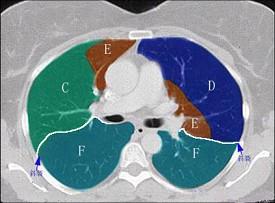

结合肺段模式(见图),选出右肺下叶的组成 ( )A、F+G+H+IB、F+G+H+I+JC、F+GD、F+G+HE、F

问题 结合肺段模式(见图),选出右肺下叶的组成 ( )

选项 A、F+G+H+I B、F+G+H+I+J C、F+G D、F+G+H E、F

答案 B